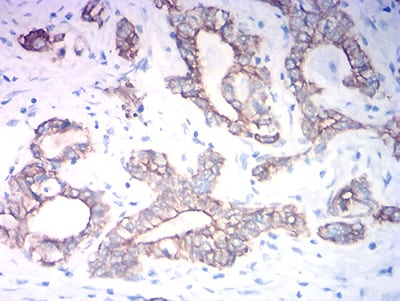

Immunohistochemical analysis of paraffin-embedded human colon cancer tissues using KRT19 mouse mAb with DAB staining.

Immunohistochemical analysis of paraffin-embedded human stomach cancer tissues using KRT19 mouse mAb with DAB staining.